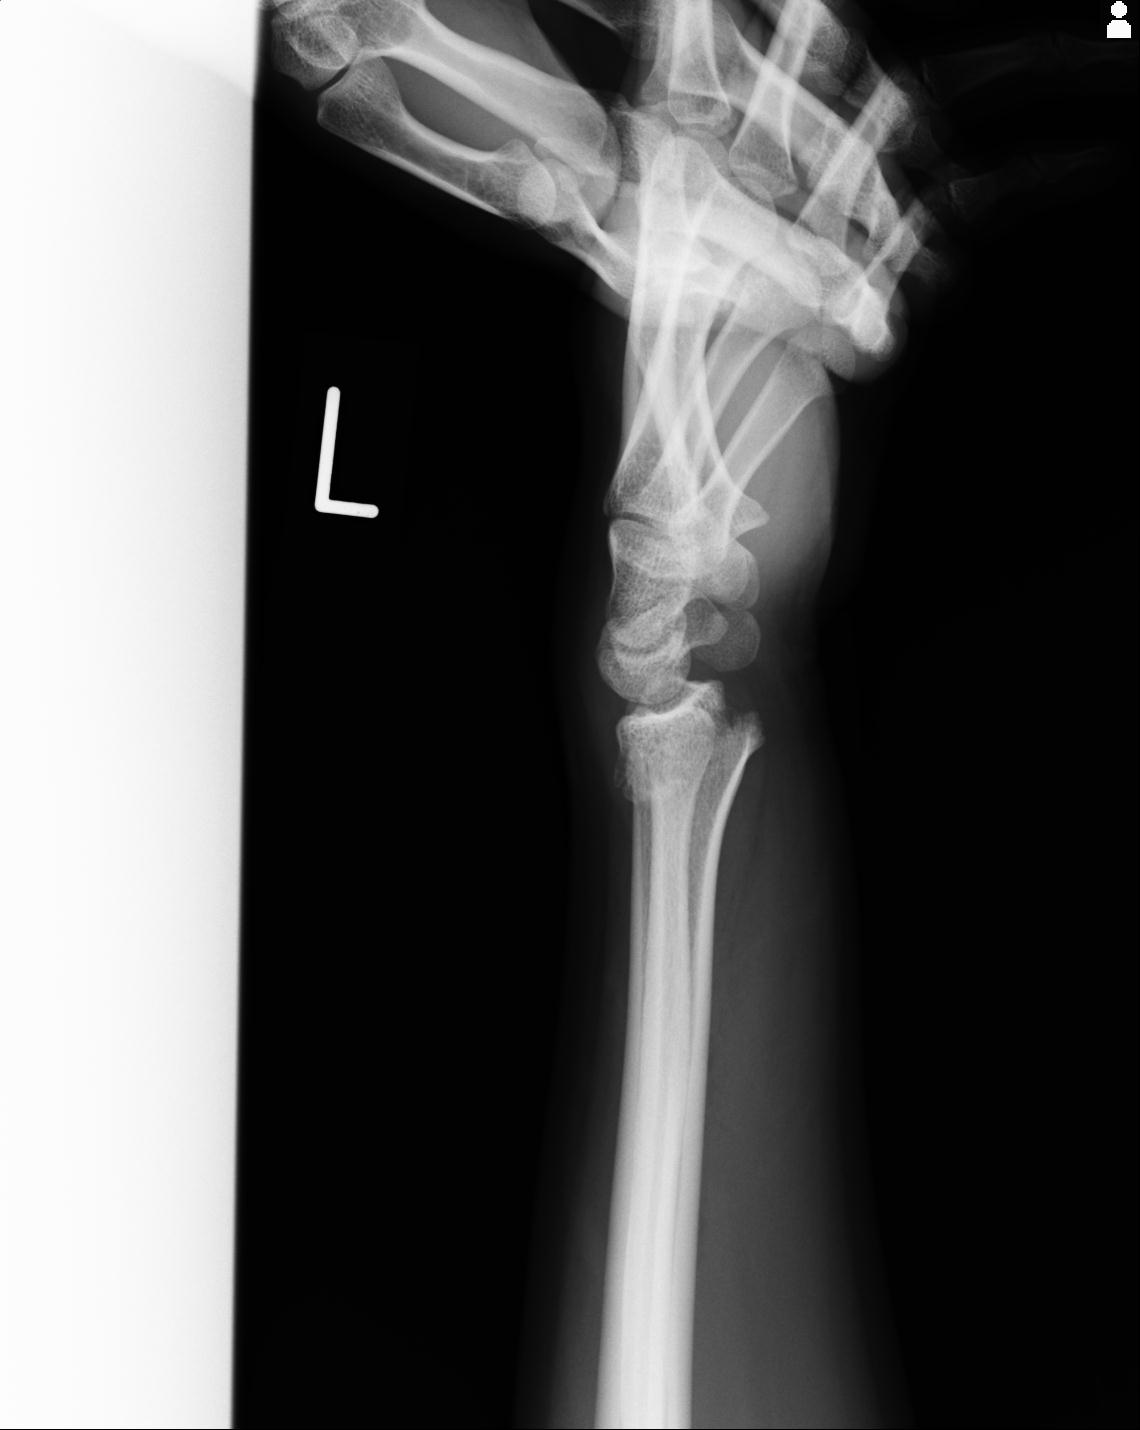

46666 1/23 両股正面+軸と右手関節 2R 76歳女性 右橈骨遠位端